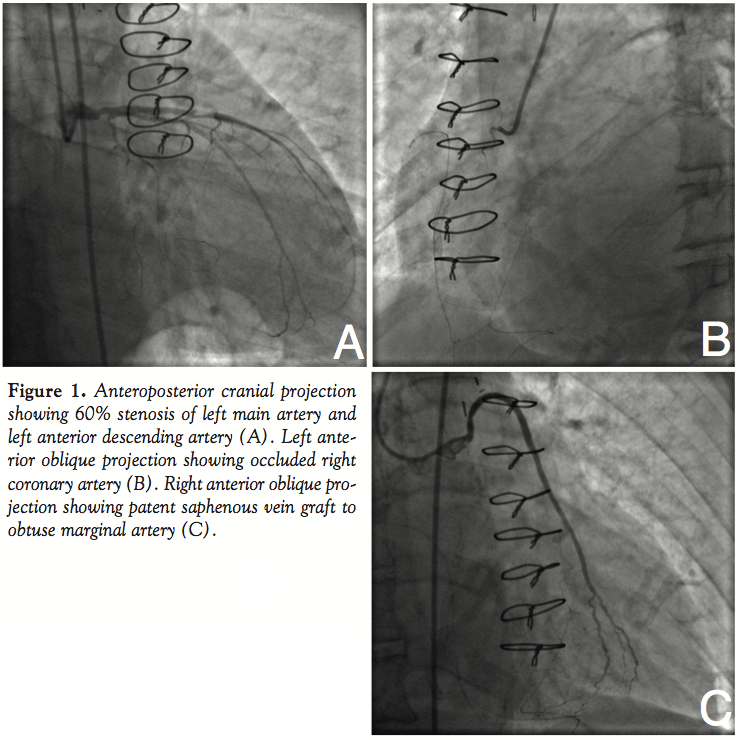

Case Report. A 60-year-old male with history of coronary artery disease was referred for a 4-month history of disabling dyspnea and orthopnea after suffering a myocardial infarction. Past history included prior PCI followed by CABG 12 years earlier. Six months prior, he underwent PCI to the SVG to left anterior descending artery (LAD) and posterior descending artery with drug-eluting stents during a non-ST segment elevation myocardial infarction. One month later he suffered another myocardial infarction and underwent coronary angiography, during which he developed ventricular fibrillation requiring defibrillation. After that we decided to manage the patient medically including aspirin and clopidogrel. Repeat arteriography at our facility showed 60% stenosis of the left main artery, 60% stenosis of the mid LAD (Figure 1A), 70% stenosis of the ostial left circumflex artery with total occlusions of the obtuse marginal and right coronary artery (RCA) (Figure 1B). The SVG to obtuse marginal was patent (Figure 1C). The SVGs to the LAD and RCA were occluded. Left ventriculogram showed an ejection fraction of 30% with inferior wall akinesis and anterior wall hypokinesis.